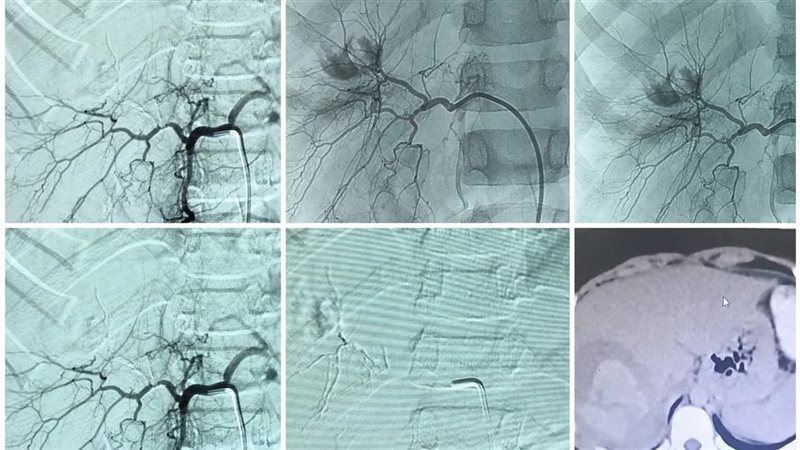

كان المستشفى، برئاسة الأستاذ الدكتور محمد عبد الحميد، قد استقبل طفل مصابا بإصابات متفرقة بعد حادث كان يقود فيه دراجة نارية "موتوسيكل"، ويعاني من تمزق حاد في الكبد أدى إلى قطع شرياني ونزيف داخلي عنيف ومهدد للحياة.

استدعى الوضع تدخلا سريعا ودقيقا، حيث يتم نقل المريض للمستشفى الرئيسي برئاسة الأستاذ الدكتور خالد عبد العزيز، ليقوم الفريق الطبي بقسم الأشعة، الذي جاء تحت إشراف الأستاذ الدكتور حسن إبراهيم مجلي، رئيس قسم الأشعة التشخيصية والتداخلية، والأستاذ الدكتور مصطفى هاشم، أستاذ الأشعة التشخيصية والتداخلية، وضم كل من الدكتور حمدي محمد إبراهيم، أستاذ مساعد الأشعة التشخيصية والتدخلية، والطبيب مصطفى طارق خلف الحسيني، أخصائي الأشعة، عاونهم الطبيب أحمد محمد حسين، طبيب مقيم بقسم الجراحة، والطبيب عمر المختار عبد العزيز، طبيب الطوارئ، ومن هيئة التمريض الأستاذ شعبان رمضان، والأستاذ عماد ناصح، فني بقسم الأشعة، استخدام تقنية القسطرة الشريانية التداخلية، وهي إجراء يتطلب مهارة عالية ودقة متناهية، وقد نجح الفريق في تحديد موقع النزيف الشرياني وإيقافه بشكل، مع الحفاظ التام على سلامة باقي الشرايين المغذية للكبد، ليعلن الفريق الطبي عقب ذلك استقرار حالة الطفل.

يعد هذا الإجراء من التدخلات الطبية المتقدمة التي تجنب المريض الجراحة المفتوحة المعقدة والمحفوفة بالمخاطر في حالات النزيف الحاد.